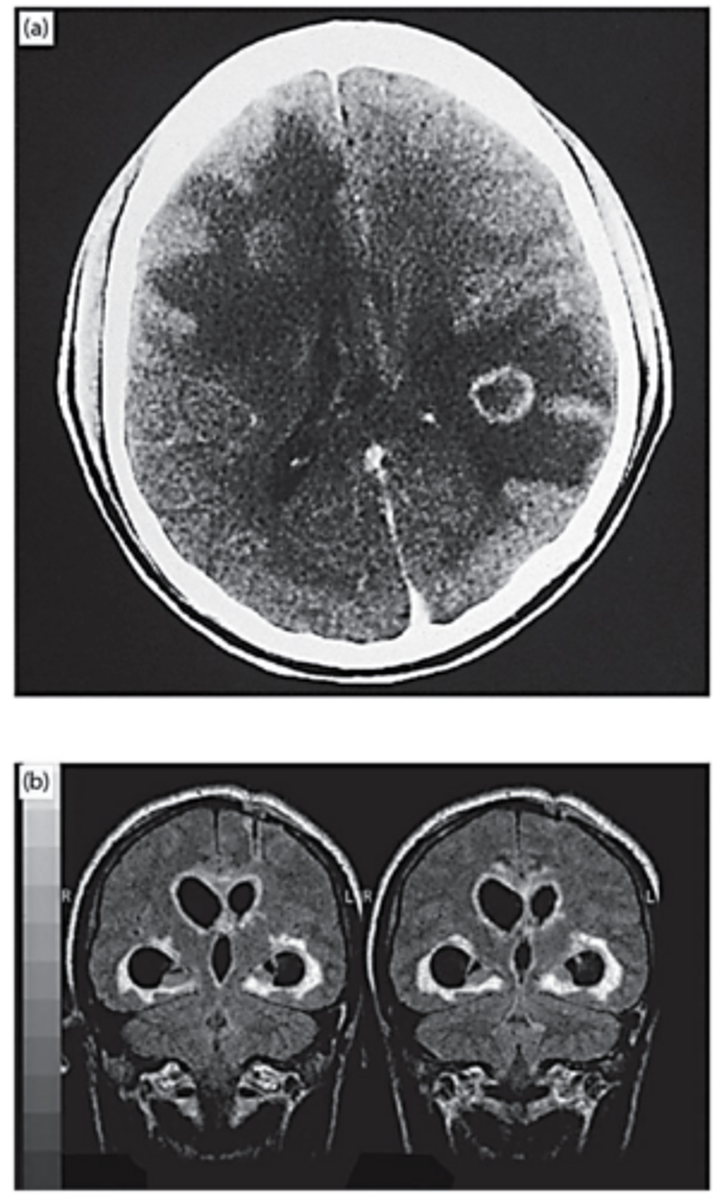

typical cerebral mass lesion with ring-enhancing lesion and surrounding edema

What does a CT scan in CNS toxoplasmosis show?

periventricular pattern of infection

What is a less common presentation of CNS toxoplasmosis on MRI scan?

a) CT scan of typical cerebral mass lesion with ring-enhancing lesion and surrounding edema

b) MRI scan showing less common periventricular pattern of infection -> histopathology showed necrosis to a depth of 1 cm, with abundant ziotes

CNS toxoplasmosis -> Toxoplasma gondii